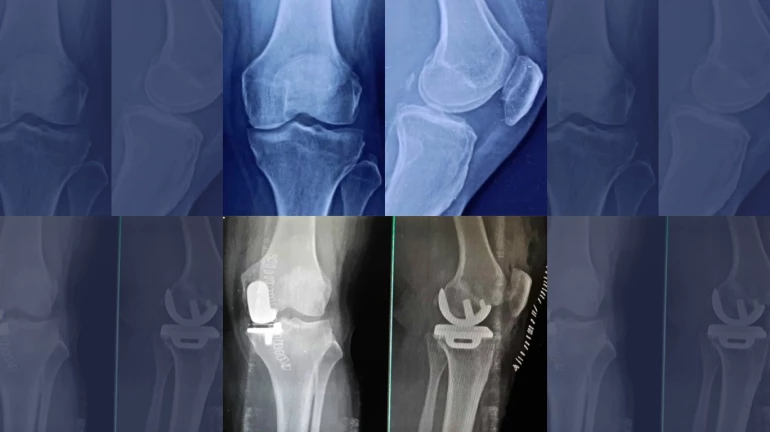

Fortunately, the patient got referred to Apex Group of Hospitals and Orthopedician & Joint Replacement Surgeon Dr. Amit Munde who reviewed his medical reports and other medical data and determined that the patient did not require a total knee replacement and instead a partial knee replacement will help him to recover from his discomfort.

Dr. Amit Munde a Joint Replacement and Sports Injury Specialist from Apex group of Hospitals says, "A partial knee replacement operation, which removes the femur (knee cap) and replaces it with artificial implants. During knee replacement surgery, bone and cartilage damaged by osteoarthritis are resurfaced with metal and plastic components. In unicompartmental knee replacement (also called partial knee replacement) only a portion of the knee is resurfaced. This procedure is an alternative to total knee replacement for patients whose disease is limited to just one area of the knee. Because a partial knee replacement is performed through a smaller incision, patients usually spend little or no time in the hospital and return to normal activities sooner than total knee replacement patients."